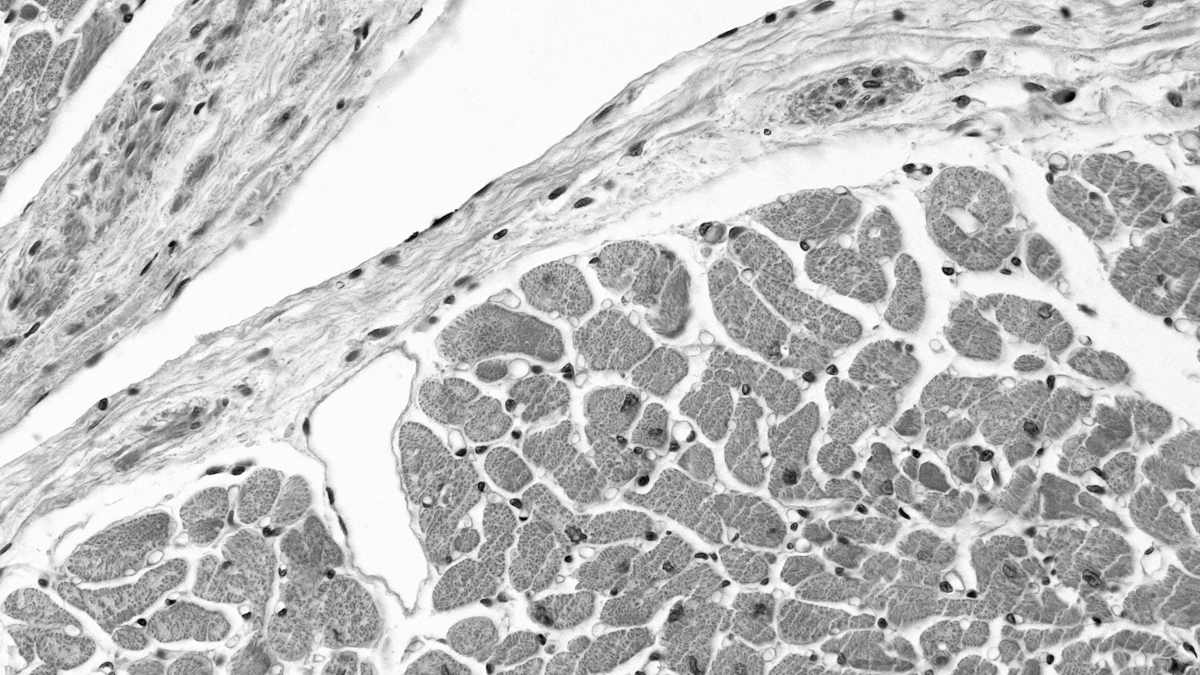

The adult human heart relies on the function of about 5 billion beating heart cells. Cardiomyocytes, the specialized muscle cells power the heart’s contractions, are killed by heart attacks, blood clots, high blood pressure, and other factors of cardiovascular disease. Cardiomyocytes have an extremely limited capacity to be repaired or replaced naturally in the body, contributing to the severity and long-term effects of heart disease. Cardiovascular disease is sadly the leading cause of hospital admission and death in the United States, and ischemic heart disease is the leading cause of death and disability worldwide.

Severe damage is done to the organ tissue after a heart attack (also called myocardial infarction), leaving a scar in the muscle that does not contract, hindering the heart’s pumping function.  Due to an insufficient means of tissue repair within an adult heart, the damage of a heart attack generally leads to a decline in heart function over time.

Cardiac stem cells are tissue-specific multipotent stem and progenitor cells capable of limited self-renewal and differentiation to coronary vessels and cardiomyocytes. Cardiac stem cells that reside in the adult heart govern myocardial homeostasis and repair injury through cardiogenesis (generation of cardiac cells) and angiogenesis (generation of blood vessels). Cardiac stem and progenitor cells hold great potential as a cell source for regenerative medicine applications around heart disease and heart failure, as these cells are proliferative yet committed to the cardiac fate, and importantly capable of further differentiation to all cells of the cardiac lineage.